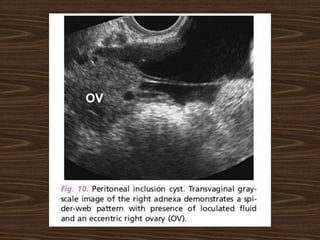

Post hysterectomy patient with

excruciating pain in abdomen

with 7cm ovarian cyst

Post hysterectomy patientwith excruciating pain in abdomen with 7cm ovarian cyst